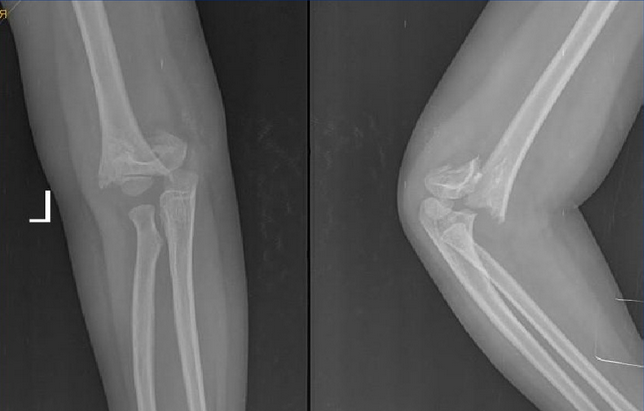

2.伸直尺偏型

外力来自肱骨髁部的前外侧,肱骨髁受暴力作用,使肱骨髁上骨折的远侧端向尺侧和后侧移位。此类骨折的内移和内翻的倾向性大,骨折移位时必须加以整复,以避免肘内翻畸形。

3.伸直桡偏型

外力来自肱骨髁部的前内侧,骨折后,远侧骨折端向桡侧和后侧移位,这种骨折不易发生肘内翻畸形。

2.X线检查:可见骨折线。